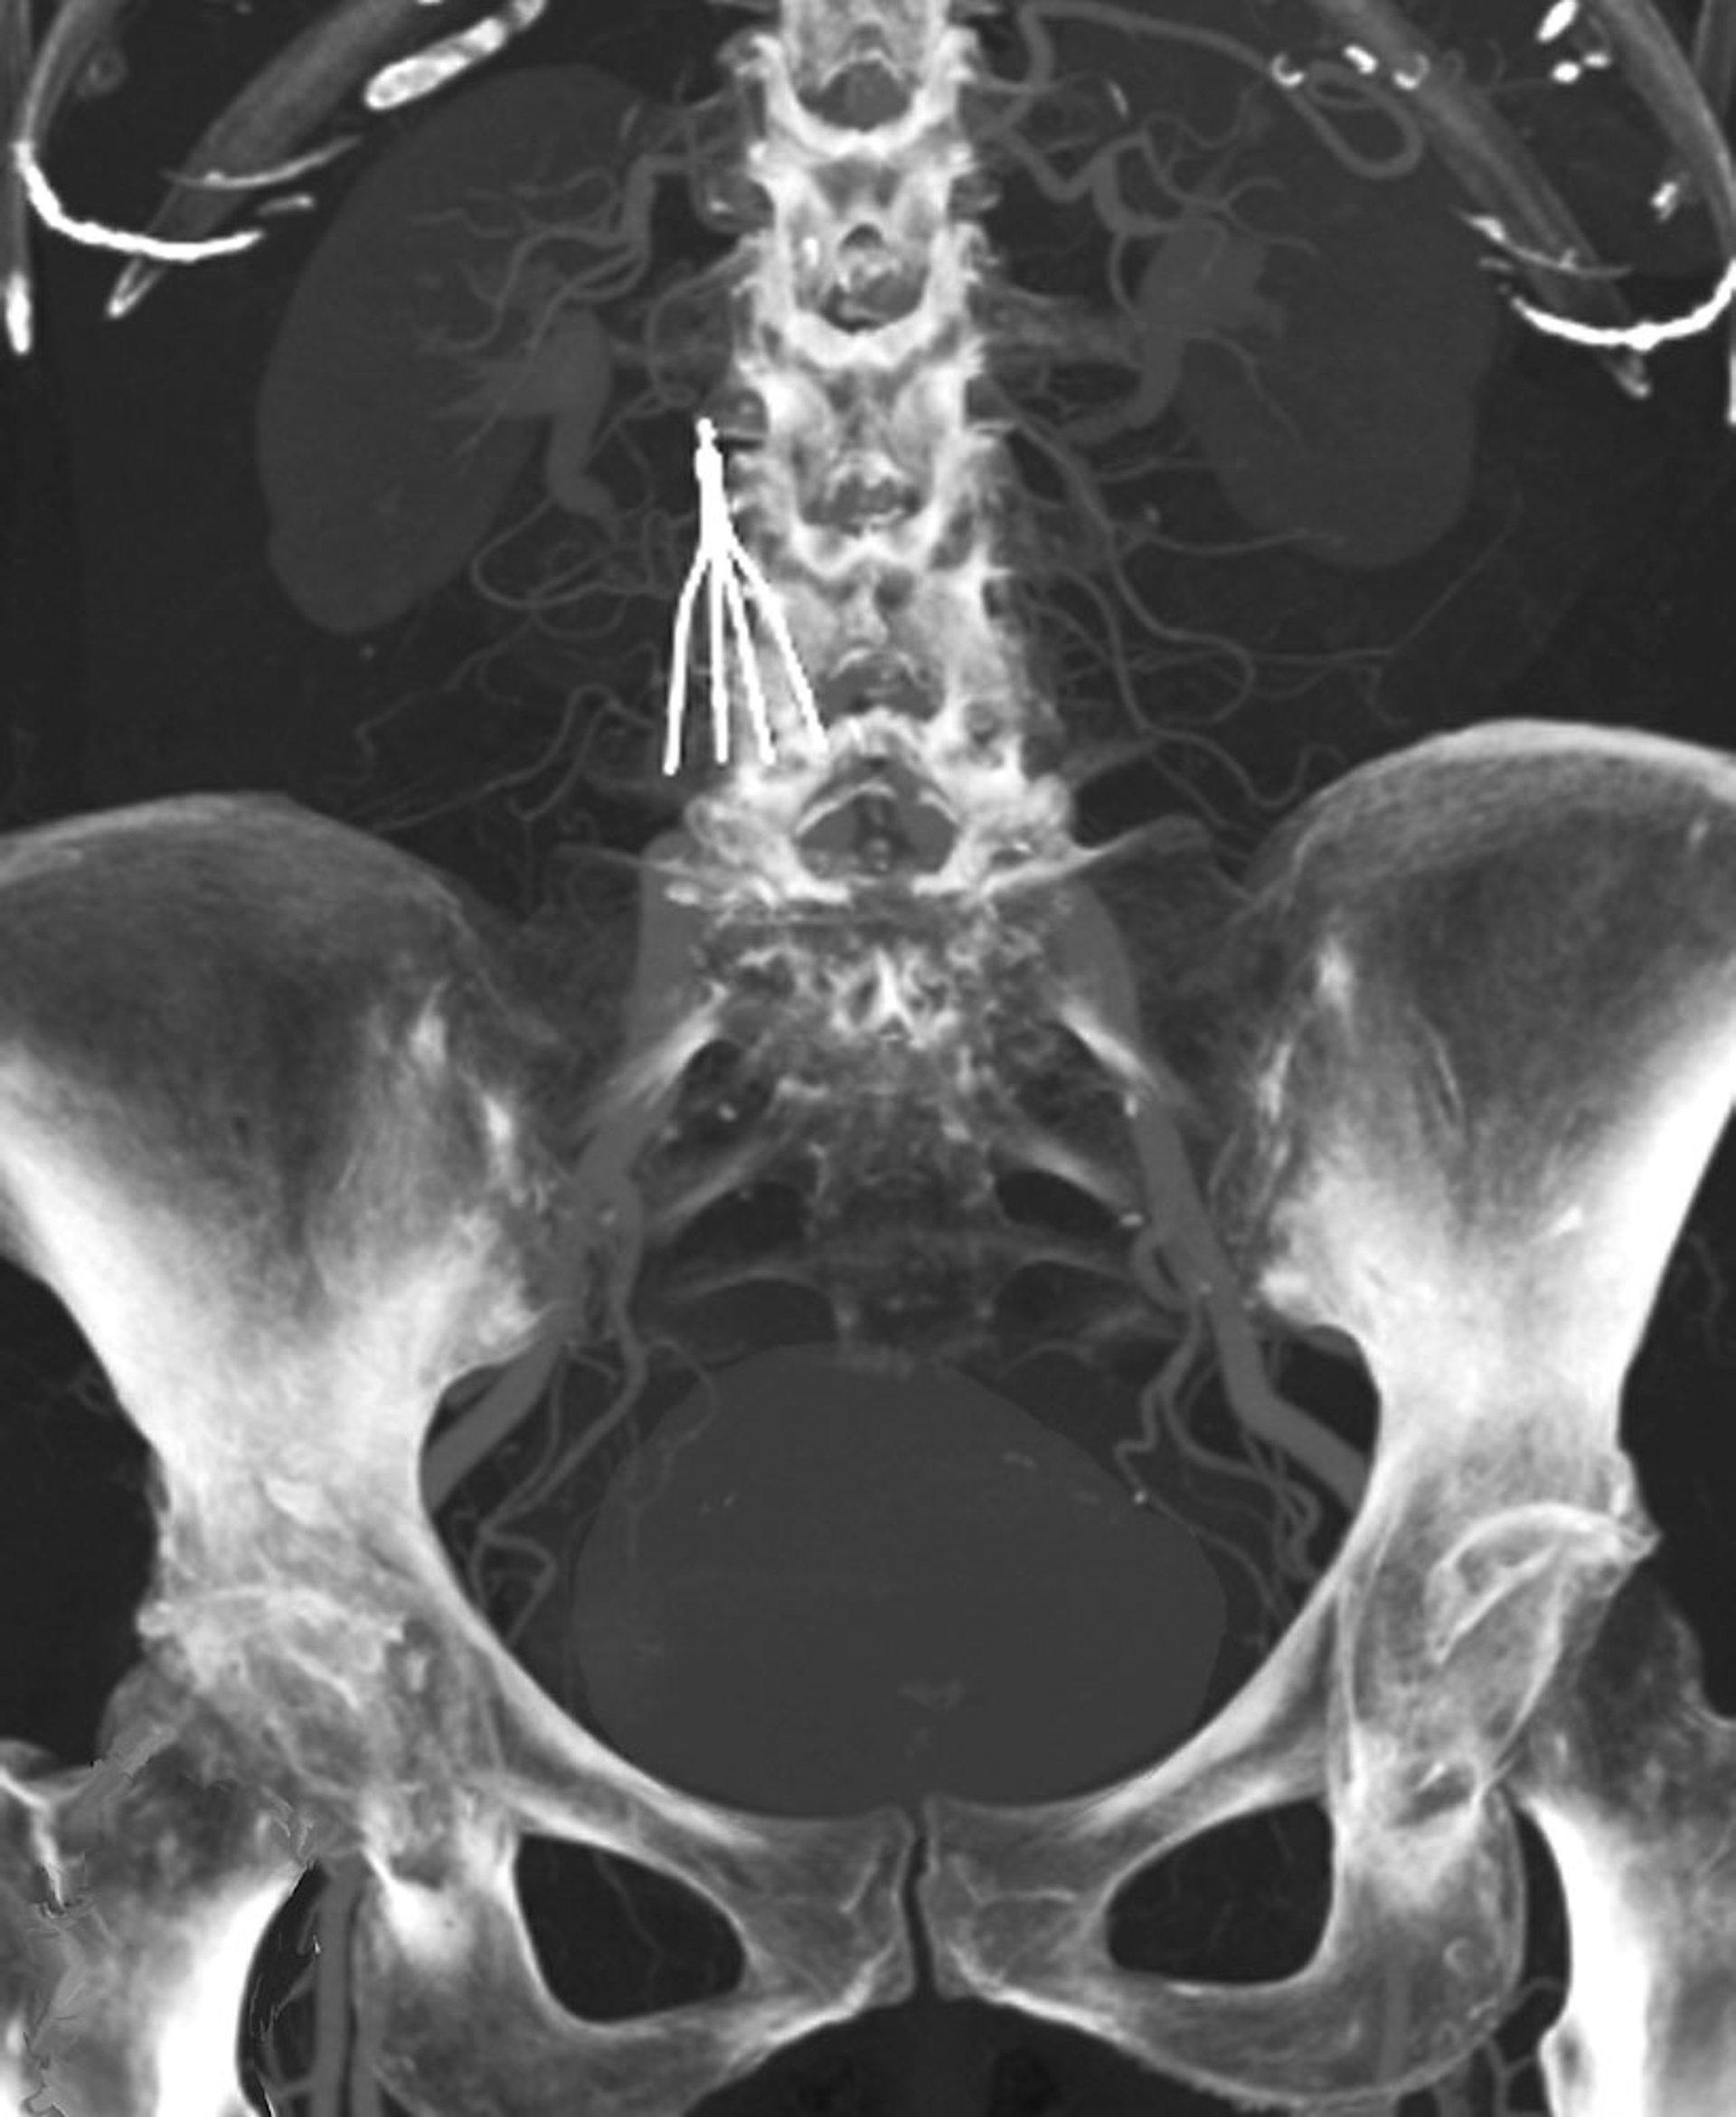

Inferior Vena Cava (IVC) Filter

This CT scan shows an implanted IVC filter.